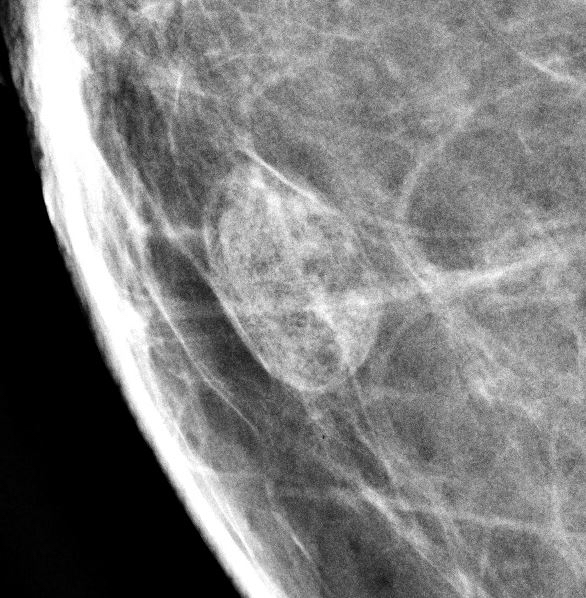

- Well circumscribed, homogenous, hyperdense or isodense, solid mass (Clin Imaging 2018;51:300)

- Typically devoid of calcifications

- Hypoechoic on ultrasound, may have posterior enhancement

- May be multilobulated

- Bilateral and multicentric tumors rare (Mod Pathol 1996;9:786, Int J Surg Pathol 2018;26:242)

Radiology images